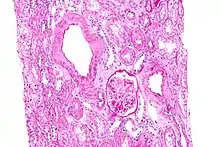

L’amylose rénale est de loin la plus précoce et la plus fréquente des complications

La substance amyloïde de la maladie périodique est formée de fibrilles identiques à la protéine de l'amylose AA, et elle intéresse de manière diffuse la paroi de toutes les artérioles, sauf celles du système nerveux central ; cette répartition est dominée par la localisation rénale..

La phase néphrotique est caractérisée par l’apparition d’un syndrome néphrotique clinique et biologique. La confirmation histologique peut être apportée par la biopsie rénale, la biopsie rectale (positive dans 75 à 85 % des cas), voire par la biopsie médullaire.